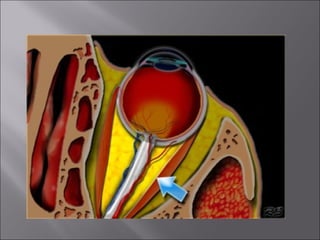

Ultrasound and CT scans provide anatomical images of the orbit, while color Doppler imaging provides visualizations of vascular structures and blood flow within lesions. These imaging techniques are used to evaluate a variety of orbital conditions involving blood vessels, infections, tumors, congenital issues, trauma, and more, and can help identify vascular disorders, thrombosis, treatment responses, and dynamic changes in benign tumors over time.